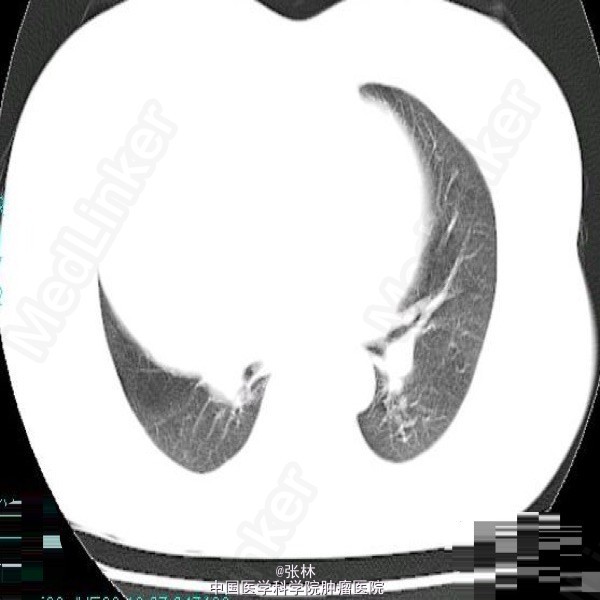

【临床病史】:患者,女性,37岁,运动后心慌、胸闷三年。右胸部呼吸音消失。叩诊呈实音。X线:右侧胸腔占位。 【影像表现】:右侧胸腔巨大囊性低密度影,大小约为109mmx118mm,边界清晰,边缘可见蛋壳样钙化,密度不均匀,CT值-35-420HU。 【影像诊断】:纵隔畸胎瘤 【最后诊断】:病理诊断:前纵隔囊性成熟性畸胎瘤。 【讨论】:畸胎类肿瘤分为囊性和实性两类,囊性畸胎瘤即皮样囊肿,多发生在前纵隔,CT为诊断该肿瘤最佳的影像学方法,可很好地显示肿块内的钙化、骨骼及脂肪成分。